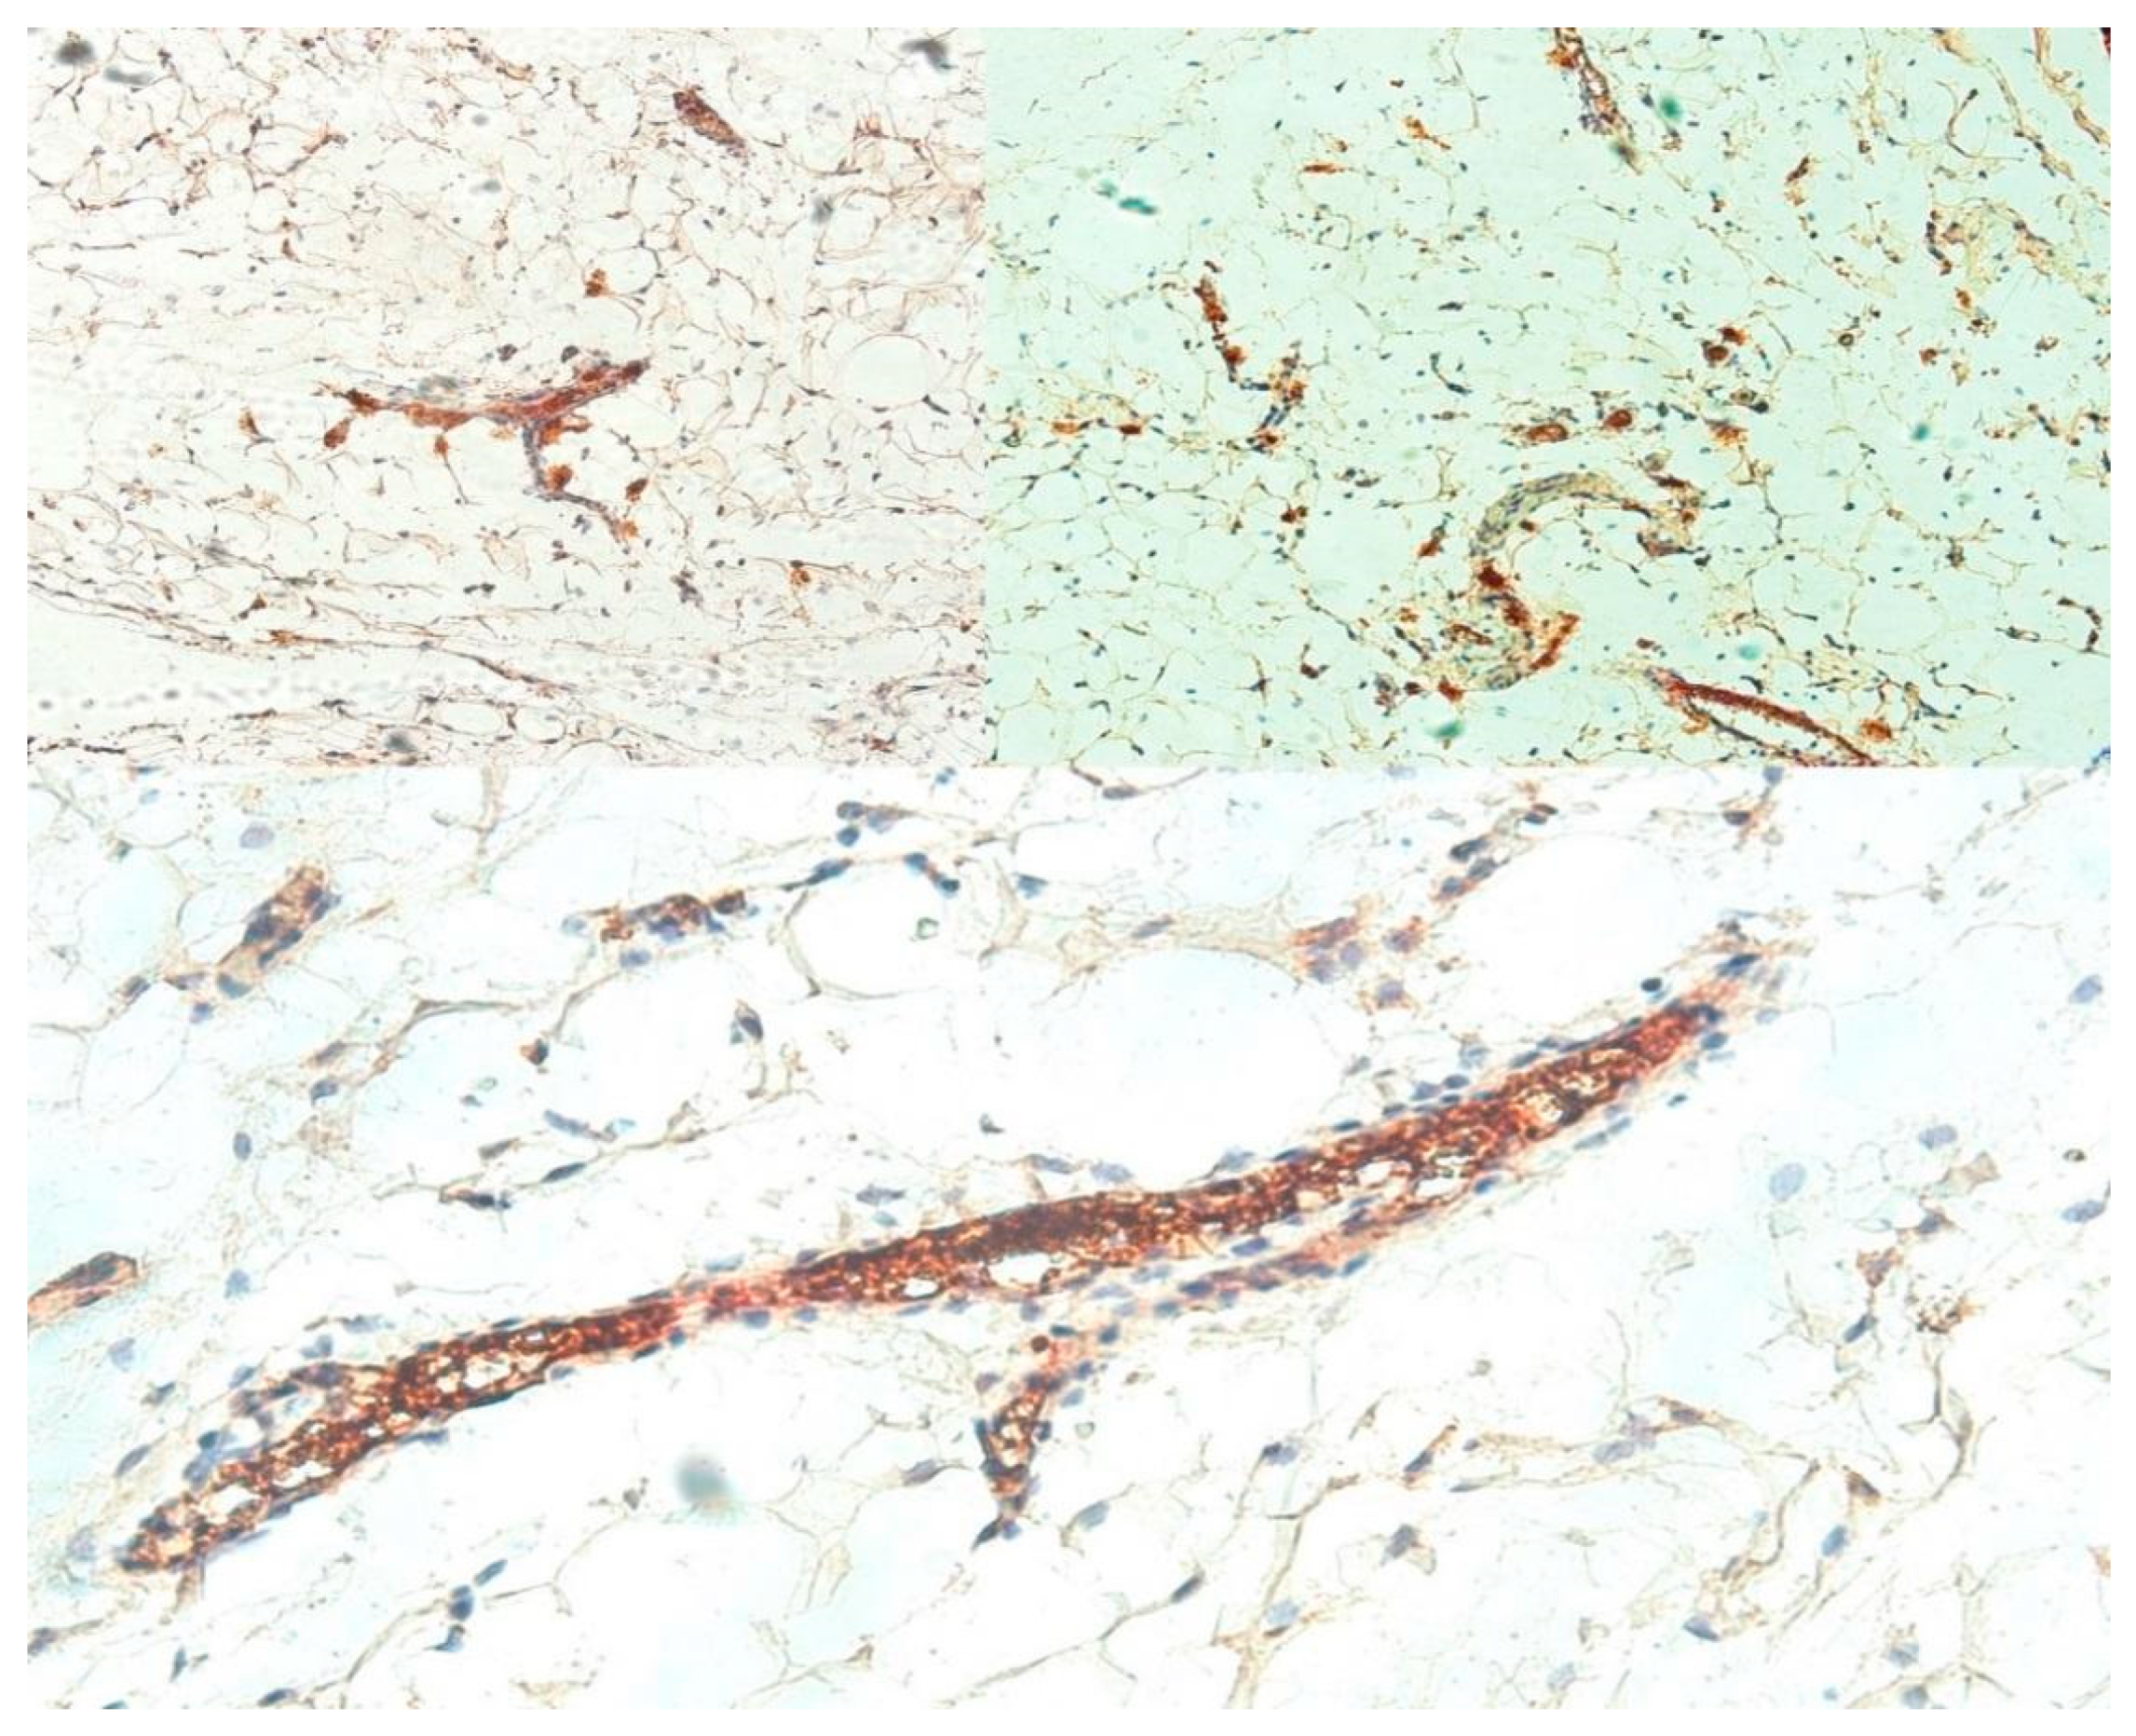

3.1.2. Assessed by Mast Cell Tryptase

3.2. Angiogenesis